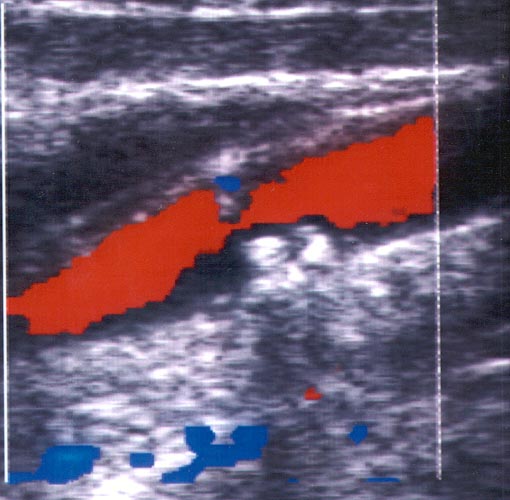

Ç Triplex åîÝôáóç ãßíåôáé áêñéâþò üðùò êáé ç Duplex åîÝôáóç ìå ôçí äéáöïñÜ üôé ç áéìáôéêÞ ñïÞ áðåéêïíßæåôáé Ýã÷ñùìç åíôüò ôïõ áããåßïõ êáé óõãêåêñéììÝíá ç öõãüêåíôñïò áéìáôéêÞ ñïÞ ( áðü ôçí êáñäéÜ) Ý÷åé êùäéêïðïéçèåß ìå êüêêéíï ÷ñþìá åíþ ç êåíôñïìüëïò ñïÞ (ðñïò ôçí êáñäéÜ) ìå ìðëå ÷ñþìá.

Ôï åðéðëÝïí äçëáäÞ óôïé÷åßï ðïõ ðñïóöÝñåé ç Triplex åîÝôáóç åßíáé ç Üìåóç áðåéêüíéóç ôïõ áõëïý ôïõ áããåßïõ ìÝóù ôçò åéêüíáò ôçò áéìáôéêÞò ñïÞò . Ç ìåãÜëç äå äéáöïñÜ ôçò Ýãêåéôáé óôçí éêáíüôçôá íá äåßîåé ôï spatial orientation ôçò áéìáôéêÞò ñïÞò. Èåùñåßôáé åðßóçò ðéü áîéüðéóôç ìÝèïäïò ãéá íá áíáäåßîåé åðéèñüìâùóç ÁèçñùìáôéêÞò ÐëÜêáò Þ ðñüóöáôï èñüìâï åðß ôïõ ôïé÷þìáôïò , ðïõ ëüãù ôçò öýóçò ôïõ õëéêïý êáé ïìïßùí õðåñç÷ïãñáöéêþí ÷áñáêôçñéóôéêþí ìå ôï áßìá äåí áðåéêïíßæåôáé óôïí Ýëåã÷ï ìå Duplex åîÝôáóç